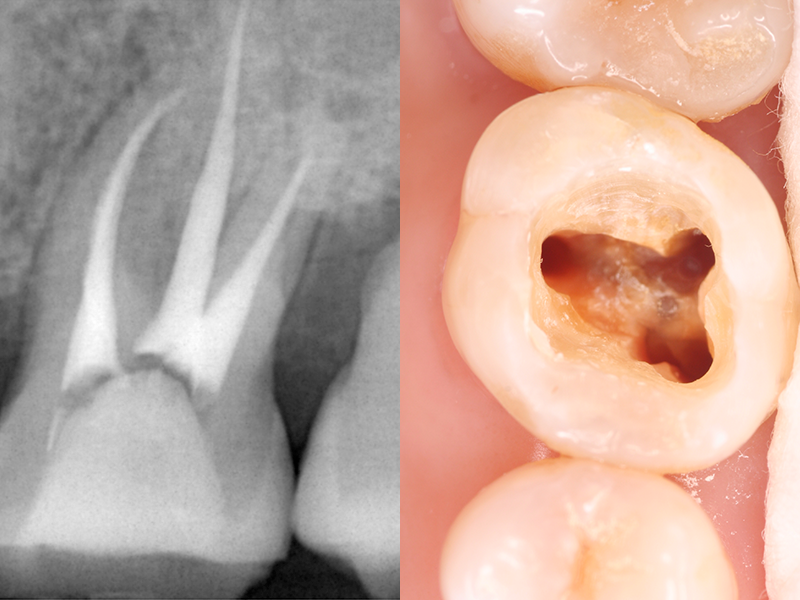

歯の神経や血管など(歯髄)が通っている根っこのような管を根管といいます。

むし歯が歯髄まで進行した場合や、歯髄が壊死してしまった場合に「根管治療」が必要になります。

細菌によって汚染された根の中を針金のようなやすり(ファイル)でこすり落として歯髄を除去し、根管内の洗浄・消毒を行い、根管内の痛みや炎症などを抑える治療です。

根管治療後は根管に薬剤を詰め、被せ物や詰め物をすることで、歯の機能を再び取り戻します。